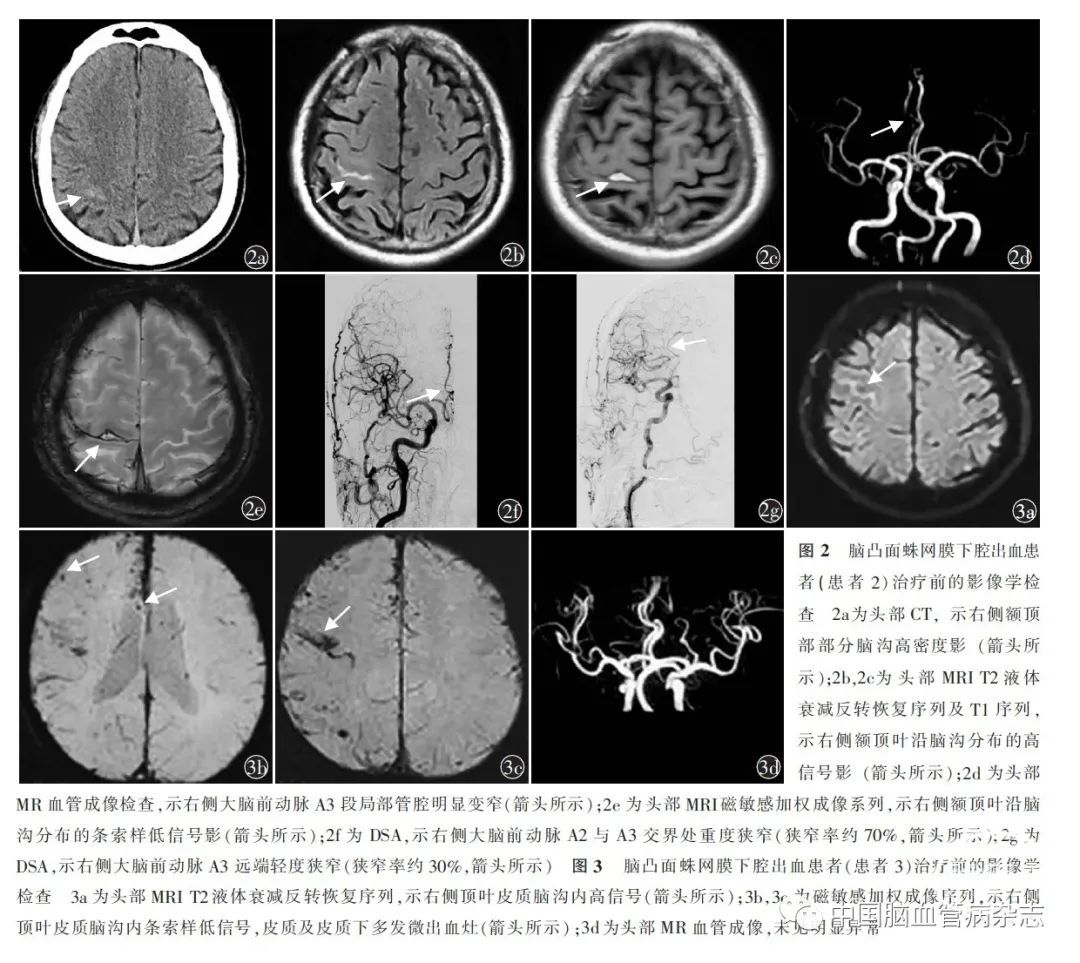

男,64 岁,因“发作性左偏身麻木无力4 d”于2021 年3 月18 日入住滨州医学院附属医院神经内科。患者入院前4 d 出现左侧偏身麻木伴左侧肢体无力,发作时左侧肢体完全不能活动,无其他伴随症状,每次发作约20 min 缓解,症状反复发作,每日发作2~3 次,门诊以“TIA”收住院。既往脑梗死病史4 个月,表现为言语欠流利,口服“硫酸氢氯吡格雷75 mg,1 次/ d”;吸烟40 年,每日约40 支,未戒烟;饮酒40 年,每日饮酒折合酒精量约40 g,未戒酒。体格检查:左侧血压130/80 mmHg,右侧血压137/94 mmHg;意识清楚,言语欠流利,脑神经功能检查(-);四肢肌力、肌张力正常,腱反射(+ + ),双侧巴宾斯基征(-),感觉及共济运动正常,脑膜刺激征(-)。头部CT 示右侧额顶部部分脑沟高密度影(图2a),提示SAH。初步诊断:SAH,脑梗死恢复期。入院后完善进一步检查,血同型半胱氨酸测定19.90 μmol/ L,葡萄糖6.59 mmol/ L;尿常规:尿葡萄糖+ + ;血常规、凝血、传染病三项未见明显异常。常规脑电图未见明显异常。简易精神状态评价量表(mini-mental state examination,MMSE)评分27 分(初中学历)。患者入院后第2 天再次发作左侧偏身麻木无力,持续约2 h 缓解,后反复发作3 次,每次持续约10 min。头部MRI 示右侧额顶部SAH(图2b,2c)。多发腔隙性脑缺血灶、梗死灶并部分软化灶形成。头部MR 血管成像示右侧大脑前动脉A3 段局部管腔明显变窄(图2d),其远端分支显影稀疏;左侧大脑前动脉A3 段局部管腔中度变窄,其远端分支显影可。磁敏感加权成像示右侧额顶叶沿脑沟分布的条索样低信号影(图2e)。头部MR 静脉成像示左侧横窦及左侧乙状窦显影较淡、较细,乙状窦局部显影不清,考虑发育所致。DSA 检查示右侧大脑前动脉A2 与A3 交界处重度狭窄(狭窄率约70% ,图2f)、A3 远端轻度狭窄(狭窄率约30% ;图2g),末梢血管未见微小动脉瘤,静脉期回流通畅。治疗上给予尼莫地平解痉、甘露醇脱水、补液等治疗,患者未再出现发作性左侧肢体麻木无力,住院13 d 出院。出院诊断:cSAH,右侧大脑前动脉A2 与A3 交界处重度狭窄,右侧大脑前动脉A3 远端轻度狭窄,脑梗死恢复期,糖耐量异常,高同型半胱氨酸血症。出院后继续口服尼莫地平,目前随访中,左侧偏身麻木及左侧肢体无力末再发作。

男,62 岁,因“发作性左侧口角伴左上肢麻木17 d”于2019 年11 月4 日就诊于滨州医学院附属医院神经内科。患者住院前17 d 无明显诱因下出现左侧口角伴左上肢麻木,以左侧拇指为著,麻木感逐渐向上波及左上肢,无其他伴随症状,症状持续数分钟自行缓解,遂至当地医院住院治疗,住院期间再次发作2 次,发作形式类似。患者既往有记忆力减退病史半年,无高血压病、糖尿病、心脏病等脑血管病危险因素,无吸烟、饮酒史,无脑血管病及记忆力减退家族史。体格检查:左侧血压125/78 mmHg ,右侧血压132/84 mmHg ;意识清楚,言语流利,对答切题,脑神经功能检查(-)。四肢肌力、肌张力正常,双侧巴宾斯基征(-),感觉及共济运动正常,脑膜刺激征(-)。MMSE 评分26 分,蒙特利尔认知评估(Montreal cognitive assessment,MoCA)量表评分19 分(初中学历)。辅助检查:外院头部MRI 示多发腔隙性脑梗死,T2 液体衰减反转恢复序列示右侧顶叶皮质脑沟内高信号,磁敏感加权成像序列示右侧顶叶皮质脑沟内条索样低信号,皮质及皮质下多发微出血灶(图3a~ 3c)。头部MR 血管成像未见明显异常(图3d)。门诊行脑电图检查示背景慢波增多,右侧后头部显著。诊断:cSAH,疑似脑淀粉样血管病,短暂性局灶性神经系统发作。给予改善认知功能等治疗,目前门诊随访中,患者口角及肢体麻木症状未再发作。

影像学表现方面,cSAH 的头部CT 可表现为大脑皮质凸面沿脑沟走行的局灶性线样高密度影,累及1 个或相邻的数个脑沟,单侧多见。中央沟受累最为常见,可达80%~ 90% ,其次为中央前沟及顶内沟[15]。对于有些出血量太少的cSAH,头部CT 可能难以分辨,需要行头部MRI 检查,尤其是梯度回波-T2*及磁敏感加权成像序列对cSAH 的检出及病因诊断有一定优势。梯度回波-T2*对于血红蛋白降解产物所致的磁敏感效应敏感,可以证实脑沟内出血性异常、既往脑实质内出血、皮质表面含铁血黄素沉积以及微出血灶。而磁敏感加权成像序列对顺磁性物质及静脉血更敏感,在发现微出血和皮质含铁血黄素沉积方面更优于梯度回波-T2* [7]。cSAH可在梯度回波或磁敏感加权成像系列中表现为沿脑沟分布的条索样边缘粗糙的低信号影。脑淀粉样血管病引起的cSAH 常可发现皮质表层铁沉积和脑叶微出血[13]。头部MR 血管成像、MR 静脉成像、CT 血管成像、DSA 等检查可发现脑血管狭窄或闭塞、血管畸形、颅内静脉窦血栓形成、烟雾病等血管异常。对脑脊液检查来说,由于出血位于脑沟中,cSAH 的腰椎穿刺阳性率并不高,多数不表现为均一血性脑脊液,若为血管炎,脑脊液可能会表现为炎性反应。本组3 例患者头部CT 或MRI 检查均发现脑沟内异常信号。第1 例患者因不能耐受未行头部MRI 检查,脑脊液检查未见异常;第2 例患者磁敏感加权成像序列示右侧额顶叶脑沟内的出血信号,但并未发现皮质表层铁沉积和脑叶微出血,不考虑脑淀粉样血管病;而第3 例患者的磁敏感加权成像序列检查,除显示脑沟内出血信号外,还发现多发脑叶微出血灶,且有认知功能障碍,符合脑淀粉样血管病诊断。